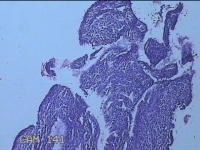

宫腔内容物

性别

女

年龄

39岁

临床诊断

异常子宫出血 重度贫血

一般病史

阴道流血20天,头晕乏力7天。

标本名称

大体所见

灰白暗红色不规则碎组织5.3x4.5x1.3cm一堆。